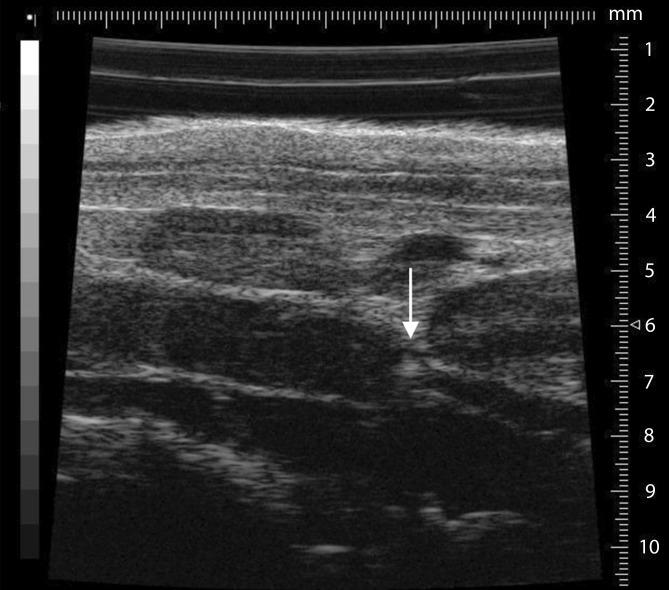

The pathogenesis of venous thromboembolism (VTE) is still not completely understood. Experimental animals in which human deep vein thrombosis can be modeled are useful tools to investigate the pathogenesis of VTE. Besides the availability of transgenic and genetically modified mice, the use of high frequency ultrasound and intravital microscopy plays an important role in identifying thrombotic processes in mouse models. In this article, an overview about the application of various new technologies and existing mouse models is provided, and the impact of venous side branches on deep vein thrombosis in the mouse model is discussed.

静脉血栓栓塞症(VTE)的发病机制仍未被完全理解。能够模拟人类深静脉血栓形成的实验动物是研究VTE发病机制的有用工具。除了转基因和基因修饰小鼠的可用性外,高频超声和活体显微镜检查在识别小鼠模型中的血栓形成过程中发挥着重要作用。本文提供了关于各种新技术和现有小鼠模型应用的概述,并讨论了静脉侧支对小鼠模型中深静脉血栓形成的影响。